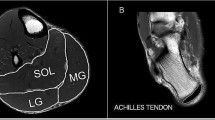

The gold standard for analyzing the architectural characteristics of human muscle is magnetic resonance imaging (MRI), but US has been actively used since 1990 to examine muscle architectural characteristics. Various studies have analyzed how the architectures of the QF, gastrocnemius, pectoralis major, and latissimus dorsi of swimmers, soccer players, sprinters, and distance runners are related to their sport performance or performance records14,17,18,23. However, none of these studies have attempted to reveal which muscle is the strongest predictor both anatomically and physiologically of the cycling power. Therefore, the primary purpose of the present study was to determine the muscle architectural characteristics of short- and long-distance cyclists and examine the relationship between these characteristics—including muscle thickness, fascicle angle, and fascicle length—of the anterior thigh and posterior leg of cyclists and the 20-s cycling power. The secondary purpose was to clarify the muscle variables that predict the cycling power by using US to measure the muscle architectural characteristics.

Real-time two-dimensional B-mode US (ECUBE 15, ALPINION Medical Systems, Seoul, Korea) with a 40-mm linear-array transducer (3.0–12 MHz; L3-12T, ALPINION Medical Systems) was used to measure muscle architecture parameters. The muscle thickness and fascicle angle were measured in the anterior thigh and posterior leg region (Fig. 2). The RF, VM, VL, and vastus intermedius (VI) in the anterior thigh region along with the Gm and Gl in the posterior leg region were also measured using US. The anatomical measurement sites are described in detail in Table 4.

The muscle thickness was defined as the distance between the superficial fascia and the deep fascia or between the deep fascia and the bone, depending on the region. The fascicle angle was defined as the angle between the fascicle and deep fascia or the bone, depending on the region. Muscles show different morphologies in the anterior thigh, including the hypertrophic region and the fascicle length of the muscle belly. Therefore, the muscle architectures of the RF, VI, and VL (including the muscle thickness and fascicle angle) were measured at the 30%, 50%, and 70% levels between the greater trochanter and the lateral epicondyle of the femur at the anterior thigh (Fig. 3). The fascicle angle of the VM was not measured because its fascicle was highly curved. The muscle thickness and fascicle angle of the Gm and Gl were measured at proximally 20% and 30% between the fibular head and the lateral malleolus.